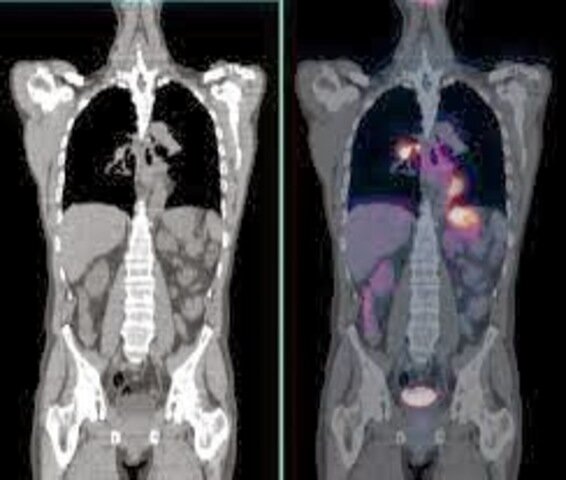

• PET-TAC

PET-TAC

Surge la combinación de PET con TAC data cuando se comprobó que utilizando la imagen de un TAC de muy baja dosis asociada al equipo se corregían con mayor precisión los problemas de atenuación intrínsecos a la imagen PET